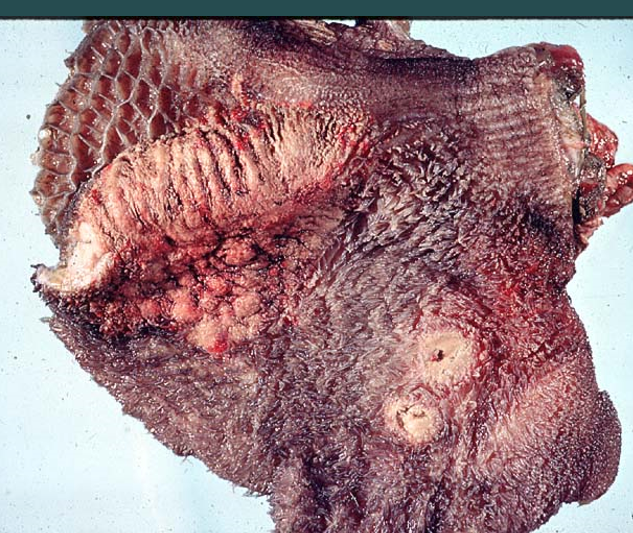

Έντερο χοίρου

Εντονότατη πάχυνση και πτύχωση του εντερικού βλεννογόνου ο οποίος ανευρίσκεται και συμφορημένος. Πρόκειται για υπερπλαστική εντεροπάθεια του χοίρου. Από lausonia intracellularis